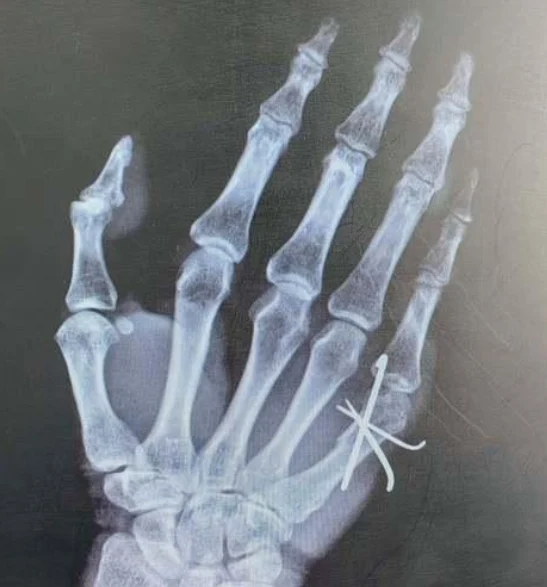

根据给出的检查报告,患者是一位76岁的老年男性,诊断为掌骨骨折。掌骨骨折是一种常见的骨折类型,尤其在老年人群中更为多见。患者的过敏史显示没有过敏反应,婚姻情况稳定。这次检查使用了0.5%罗哌卡因和2%利多卡因为局部麻醉药品,以帮助缓解疼痛。

掌骨骨折的治疗方案通常包括非手术和手术治疗。首先,可以通过石膏固定或夹板固定来确保骨折部位的稳固,这通常是简单非移位性骨折的首选治疗方法。在固定的过程中,患者可能需要服用镇痛剂来缓解疼痛。

对于复杂的或者移位性骨折,可能需要进行手术治疗,使用钢板、螺钉或其他内固定装置来复位并固定骨折部位。术后的护理也是治疗成功的关键一环,康复锻炼和日常护理能够帮助骨折部位更好地恢复。

研究显示,内固定装置的使用在掌骨骨折的恢复过程中,能够显著提高骨折的愈合速度和手部的功能恢复。《临床骨科与相关研究》中的一篇论文指出,及时应用内固定治疗能够显著减少并发症和后遗症的发生。